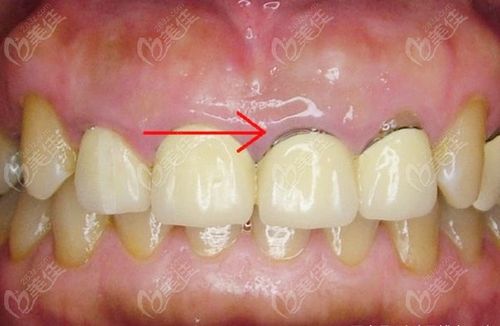

医生,医生怎么我的烤瓷牙上有个黑线,怎么办.

牙齿有黑线要做什么修复

2,全瓷牙不像烤瓷牙那样会对邻牙有磨损.3,全瓷牙没有牙龈"黑线"问题.